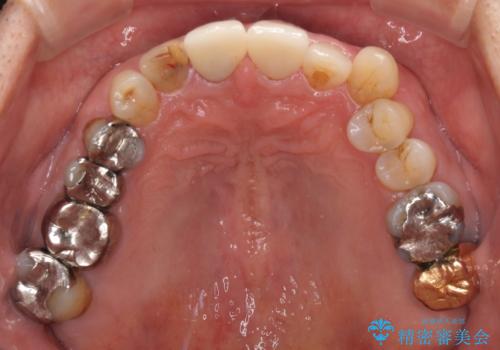

- 前歯がぐらつくことを主訴にご来院された患者様です。ご本人は抜歯と考えており、インプラント以外の治療をご希望でした。しかしながらぐらついていた原因は、古い差し歯が取れかけていたことでした。

遠方から通院されること、仕事上短期間で治療したいとのことを考慮して、残っている歯はかなり小さいものの、保存すべきと判断して当日処置から行いました。

西日本から新幹線でご来院された患者様です。前歯は都内の医院でやりたいとのことで、はるばる通院してくださいました。通院回数が最小限になるよう工夫しました(1回あたりの時間は長くなります)。

残っている歯が小さいと、差し歯はぐらつきやすくなりますが、その形態によっては抜歯を回避できることがあります。